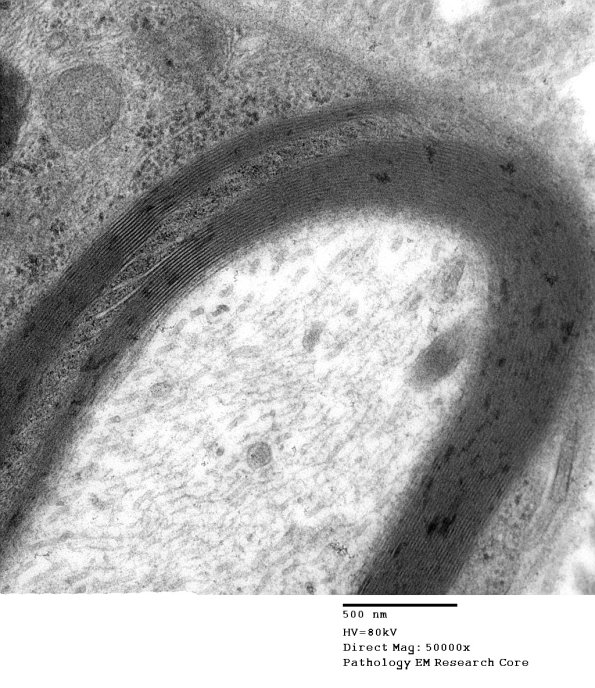

Higher magnification of image #6A2. (electron micrograph)